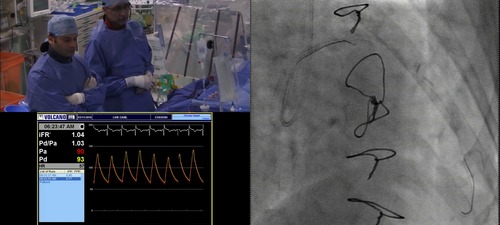

Sayan Sen and Iqbal Malik demosntrate how to prepare the pressure wire to ensure robust and reliable physiological measurements

• Use of iFR to assess ischaemia

• Use of iFR-Scout to map out physiological gradients along the lengh of the vessel